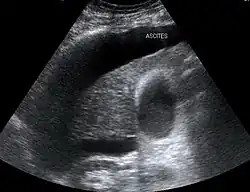

Ascitis

La ascitis es la acumulación anormal de líquido en la cavidad peritoneal (abdomen).[3][4] Técnicamente, es más de 25 ml de líquido en la cavidad peritoneal, aunque pueden ocurrir volúmenes superiores a un litro. Los síntomas pueden incluir aumento del tamaño abdominal, aumento de peso, malestar abdominal y dificultad para respirar. Las complicaciones pueden incluir peritonitis bacteriana espontánea.

En el mundo desarrollado, la causa más común es la cirrosis hepática.[4] Otras causas incluyen cáncer, insuficiencia cardíaca, tuberculosis, pancreatitis y bloqueo de la vena hepática. En la cirrosis, el mecanismo subyacente implica presión arterial alta en el sistema portal y disfunción de los vasos sanguíneos. El diagnóstico generalmente se basa en un examen junto con una ecografía o una tomografía computarizada. El análisis de líquido puede ayudar a determinar la causa subyacente.